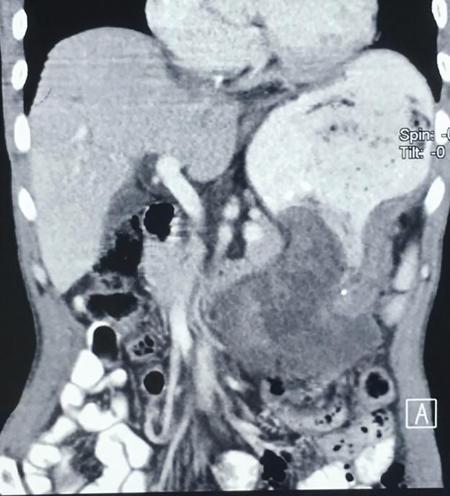

Image

Fig 7.4.5.1 Barium study of the patient.

Fig 7.4.5.2 CECT of the patient.

Fig 7.4.5.3 CECT of the patient.

Observations

Barium study shows large filling defect in the antrum forming acute angles with the wall. Undulating contour is seen along greater curvature with ulceration of overlying mucosal irregularity.

CECT shows a large lobulated mass involving lesser curvature and antrum with marked wall thickening along distal greater curvature.

Diagnosis

Carcinoma stomach.